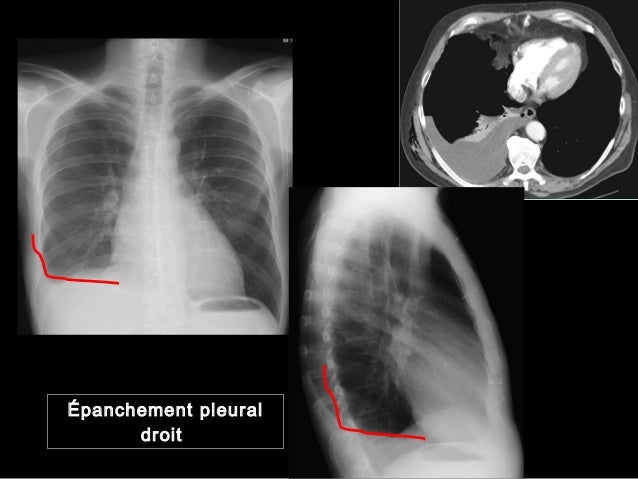

Www Ch Carcassonne Fr Imgfr Files Drainage thoracique powerpoint mr glapiack Pdf